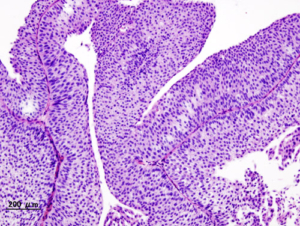

Il nuovo dispositivo TAR-200 ha ottenuto un tasso di risposta completa mai visto prima, pari all’82% nei pazienti con carcinoma uroteliale ad alto rischio, non muscolo invasivo, non più responsivi all’immunoterapico BCG.

Il tumore della vescica non muscolo invasivo ad alto rischio può recidivare nonostante le cure standard con asportazione e l’utilizzo dell’immunoterapico BCG. In questi casi l’opzione standard è la cistectomia radicale, un intervento invasivo e non scevro da rischi e complicanze. Lo studio SunRISe-1 mostra che il nuovo dispositivo TAR-200 può offrire un’alternativa efficace, permettendo nella maggior parte dei casi di evitare la rimozione della vescica.